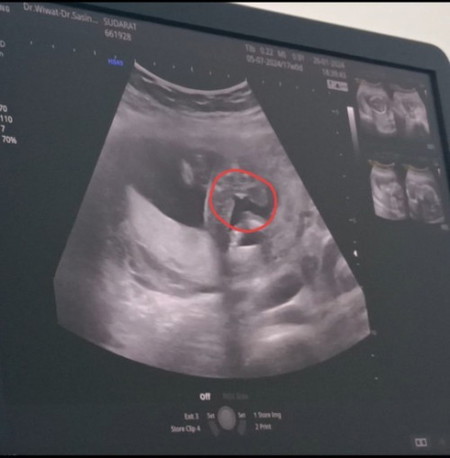

ตั้งครรภ์ 17 สัปดาห์

ช่วยแม่ดูหน่อยค่ะ ช. หรือ ญ หมอยังไม่กล้ายืนยัน 100% พูดแค่ว่าเหมือนจะเป็น ญ แต่ก็คล้ายเด็ก ช เลยบอกแม่ขอรอยืนยันเดือนหน้าค่ะ